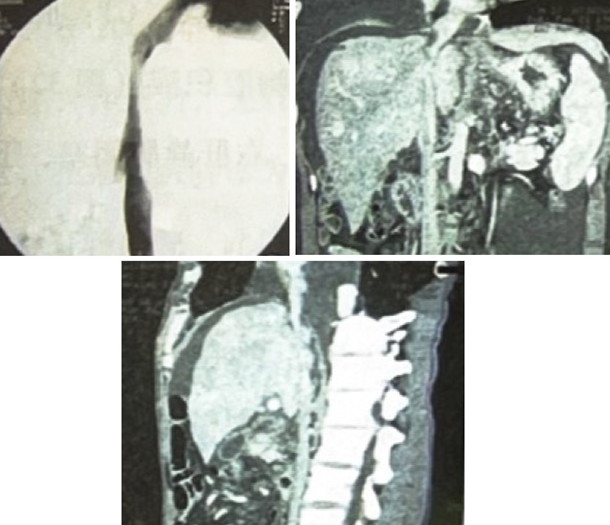

肝静脉、下腔静脉造影:中肝静脉显示,左肝、右肝静脉闭塞,下腔静脉全段充盈不良,显示不清(图3)。

图3 肝静脉和下腔静脉造影

因该患2年前发病时即有腹水,当时肝功、凝血三项、血常规均正常,既往无肝炎、血吸虫病、结核、肾病及心脏病病史,无大量饮酒史,2年期间病情无明显恶化,所以我们高度疑诊为布-加综合征,并行肝静脉、下腔静脉超声检查,结果证实了我们的诊断,此后又行肝静脉、下腔静脉造影进一步确诊,经球囊导管扩张左肝静脉,患者双下肢浮肿消退,胸、腹水消失,肝功恢复正常。